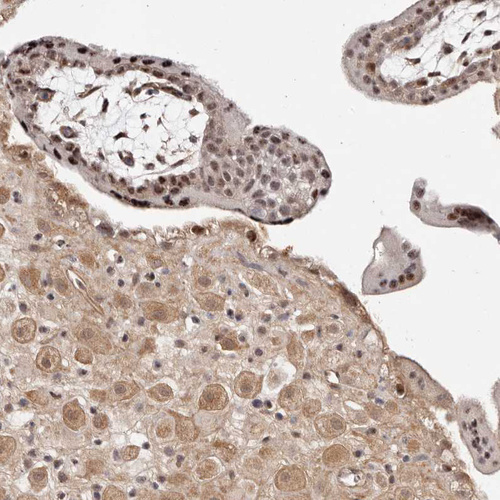

Immunohistochemical staining of human testis shows moderate nuclear positivity in Leydig cells.